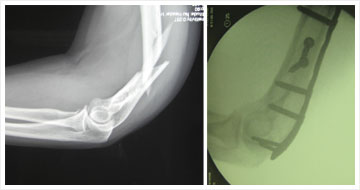

Examples: X-ray of broken humerus

Repair of torn biceps tendon